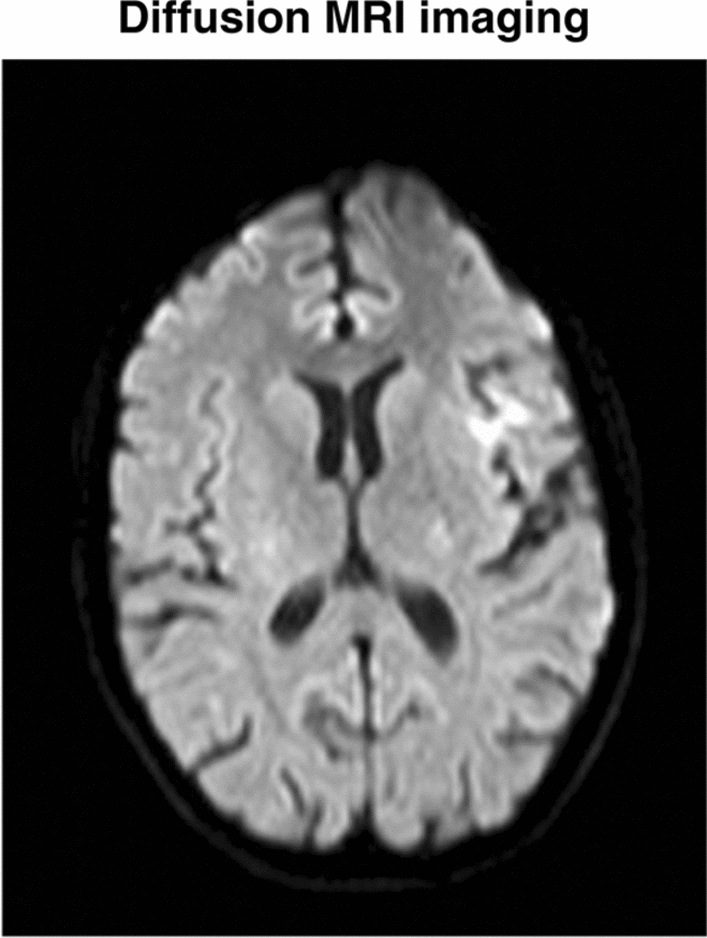

Upon admission to the stroke unit, she had an NIHSS score of 2 and a persisting deficit affecting the VII cranial nerve. This picture rapidly improved until normalization with an NIHSS score of 0. The neuroradiological investigations, in particular the brain magnetic resonance imaging (MRI), showed an ischemic lesion in the left insulae and fronto-opercolar cortex, no longer symptomatic at the time of the scan. In figures reported below diffusion MRI and perfusion CT results are shown (Figs. 2 and 3).

Fig. 2.

MRI diffusion imaging that shows the appearance of an ischemic lesion in the left insulae and fronto-opercolar cortex